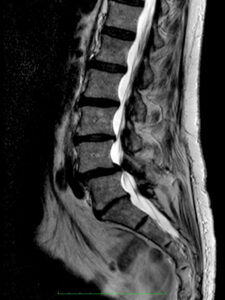

Bilder:

MRT: Wirbelgleiten LW4/5 mit absoluter Spinalstenose

Die Erfolgsrate der Stabilisierungsoperationen hängt sehr von den vorbestehenden Beschwerden, der Ausprägung des Befundes und der beruflichen Belastung ab. Leichte körperliche Tätigkeiten sind i. d. R. wieder nach drei bis sechs Monaten möglich.